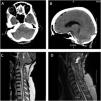

Chiari malformations (CM) are often diagnosed in childhood and younger adults, with an incidence of only 0.77% in adult populations. Patients with CM may develop syringomyelia and increased intracranial pressure (ICP) due to cerebrospinal fluid (CSF) obstruction and altered fluid dynamics at the cervicomedullary junction. We describe the case of a 65-year-old female presenting with an angionegative subarachnoid hemorrhage (SAH) with concomitant new diagnosis of CM type I with syringomyelia. After ruling out any aneurysm or vascular malformations, she underwent a suboccipital craniectomy for a Chiari decompression with a C1 laminectomy. There were no complications with the surgery and her symptoms improved. This case report highlights the unusual presentation of a CM.